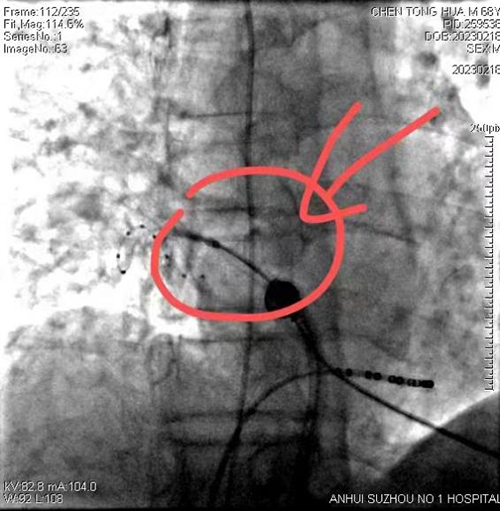

而说到陈大爷的手术,不得不提到今年2月份。68岁的陈大爷来到我院心内一科就诊,说他反复胸闷、胸痛有3年时间了,最近3个月症状明显加重。我院心内一科医生发现情况不对,随即让陈大爷入院治疗,经检查发现陈大爷为阵发性心房颤动。由于病情严重,当时陈大爷近一个月时间,甚至连生活都不能自理。而在家中自服治疗药物(胺碘酮)期间又发生心房颤动,说明抗心律失常药物不能解决其问题。心房颤动大多是藏匿于肺静脉的异常电活动引起的,除去药物治疗外,还可进行导管消融手术对肺静脉完成隔离,让心脏回归正常节律。经我院心脏中心户学敏副院长团队的充分评估病情后,为患者选择了一种特殊的治疗方式——“冷冻球囊消融”。

冷冻球囊消融是将液态制冷剂由体外沿导管输送到末端的球囊,制冷剂气化,使消融部位温度骤然降低,局部组织细胞坏死,完成肺静脉隔离,消除房颤。相对于传统的射频消融手术,冷冻消融手术对于医生的技术要求更高,但对患者来说创伤小,手术时间短,主观感受更好,大大减轻了疼痛感。

在充分的术前准备后,心脏中心手术团队在户学敏副院长的带领下,心内一科主任闫宜亮、主治医生胡金涛、周博文的完美配合下,为陈大爷进行了房颤冷冻消融术。手术在局麻下完成,术程顺利,用时仅半小时。返回病房后六小时,陈大爷即可下床活动。第二天查房时,陈大爷精神状态特别好,说他术后再也没感觉到胸闷、胸痛的症状了,食欲也大大增加,当天的早饭吃了以前一天的饭量。陈大爷的一句话逗得病房的人都笑了起来……